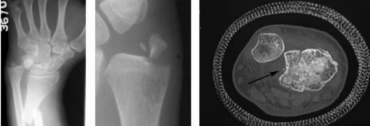

下尺橈關節脫位的診斷除依靠損傷機制、臨床表現及影像表現外,某些損傷也可提示存在下尺橈關節韌帶的損傷。包括蓋氏骨折、尺骨莖突基底部的骨折及CT橫斷位乙狀切跡的撕脫骨折。

從左到右:

蓋氏骨折、尺骨莖突基底部骨折、乙狀切跡撕脫骨折